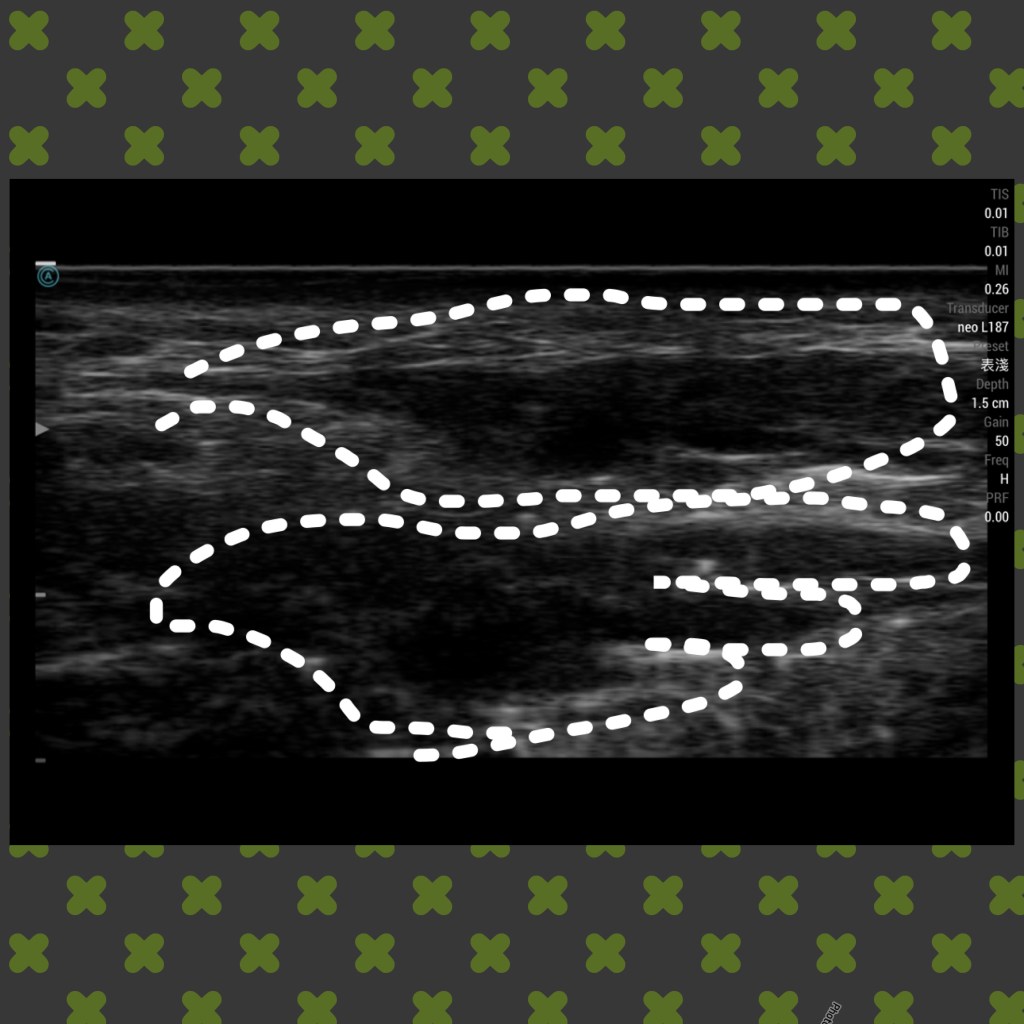

- 基本超音波掃描判別:組織與材料的狀態分布提供精準治療

玻尿酸填充的不自然及過量可以透過超音波引導注射溶解酶改善

下圖: 玻尿酸填充造成饅化與水腫